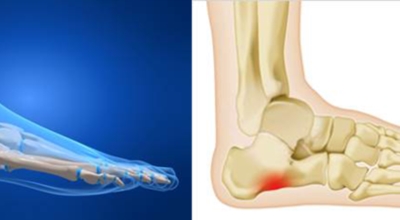

족저 근막이란 발가락 시작지점부터 발뒤꿈치뼈까지 발바닥 전체를 감싸고 있는 두꺼운 막입니다. 족저 근막은 발바닥 아치를 유지해 발바닥이 지면을 내딛음으로써 발생하는 충격을 흡수하는 중요한 역할을 수행하는데요 이 족저 근막에 일차적으로 서서히 조직 손상이 일어나고 계속적인 활동으로 인해 염증이 커지면서 발 뒤꿈치 부근 통증을 일으키게 되는데요 염증은 무리하고 반복적인 동작, 과도한 사용으로 마찰에 의해 발생합니다.

족저 근막염은 염증에 의한 손상 및 통증을 유발하는 질환인데요 족저 근막염 증상은 일반적인 발뒤꿈치 통증 하글런드 병변의 기형으로 알려져 있으며 아킬레스 건과 관련이 깊습니다. 특히 근육이 덜 풀린 아침 시간 대는 보행 시 날카롭고 바늘로 찌르는 듯한 심한 통증을 느끼게 된다고 합니다. 그러나 아침 시간 대를 지나 오후에 접어들면서 어느 정도 통증은 서서히 감소하기 시작한다고 하는데요 초기 증상이 나타난다면 반드시 전문의를 찾아 조기에 치료하는 것이 바람직합니다.